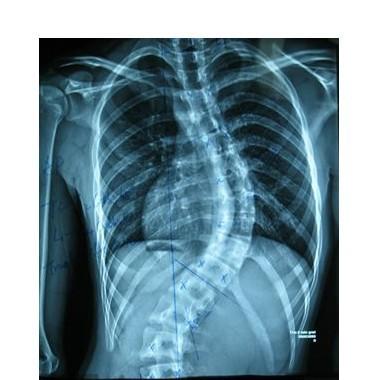

AS ①晚期 ②重度 病史:5年+

治疗后骶髂关节疼痛消失,腰椎前屈、背伸侧弯活动自如,膝关节无压痛感,复查血沉、C反应蛋白、等各项检查均已达到临床康复的标准。